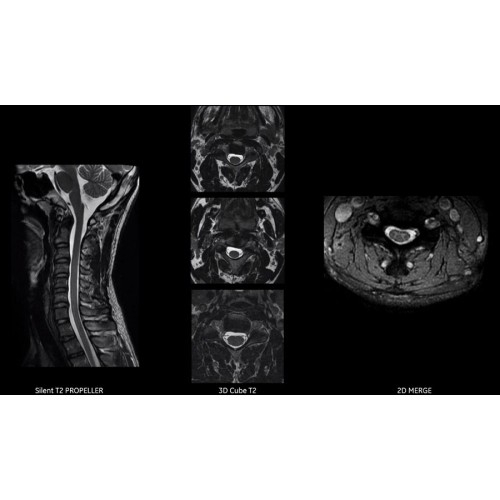

Диагностические возможности аппарата

Многофункциональность исследований

МРТ аппарат GE SIGNA Voyager 1.5T позволяет проводить полный спектр магнитно-резонансных исследований, включая нейровизуализацию, исследования опорно-двигательного аппарата, органов брюшной полости и малого таза, а также специализированные кардиологические программы.

Поддержка современных протоколов

Аппарат поддерживает все актуальные диагностические протоколы и совместим с современными медицинскими информационными системами, обеспечивая интеграцию в цифровую инфраструктуру клиники.